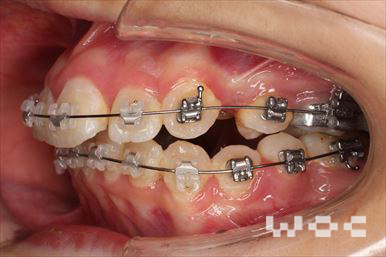

出っ歯エッジワイズ装置

特に装置の希望はなかったので、エッジワイズ装置を選択。

歯の移動量が大きいので歯根吸収の可能性がありましたが、目立った吸収は見られませんでした。-

治療中1

- 年齢:17歳女性

- 主訴:出っ歯、前歯のガタガタが気になる

- 基本矯正料金:78万円

- 治療期間:1年2ヶ月

- 抜歯部位:上顎両側第一小臼歯